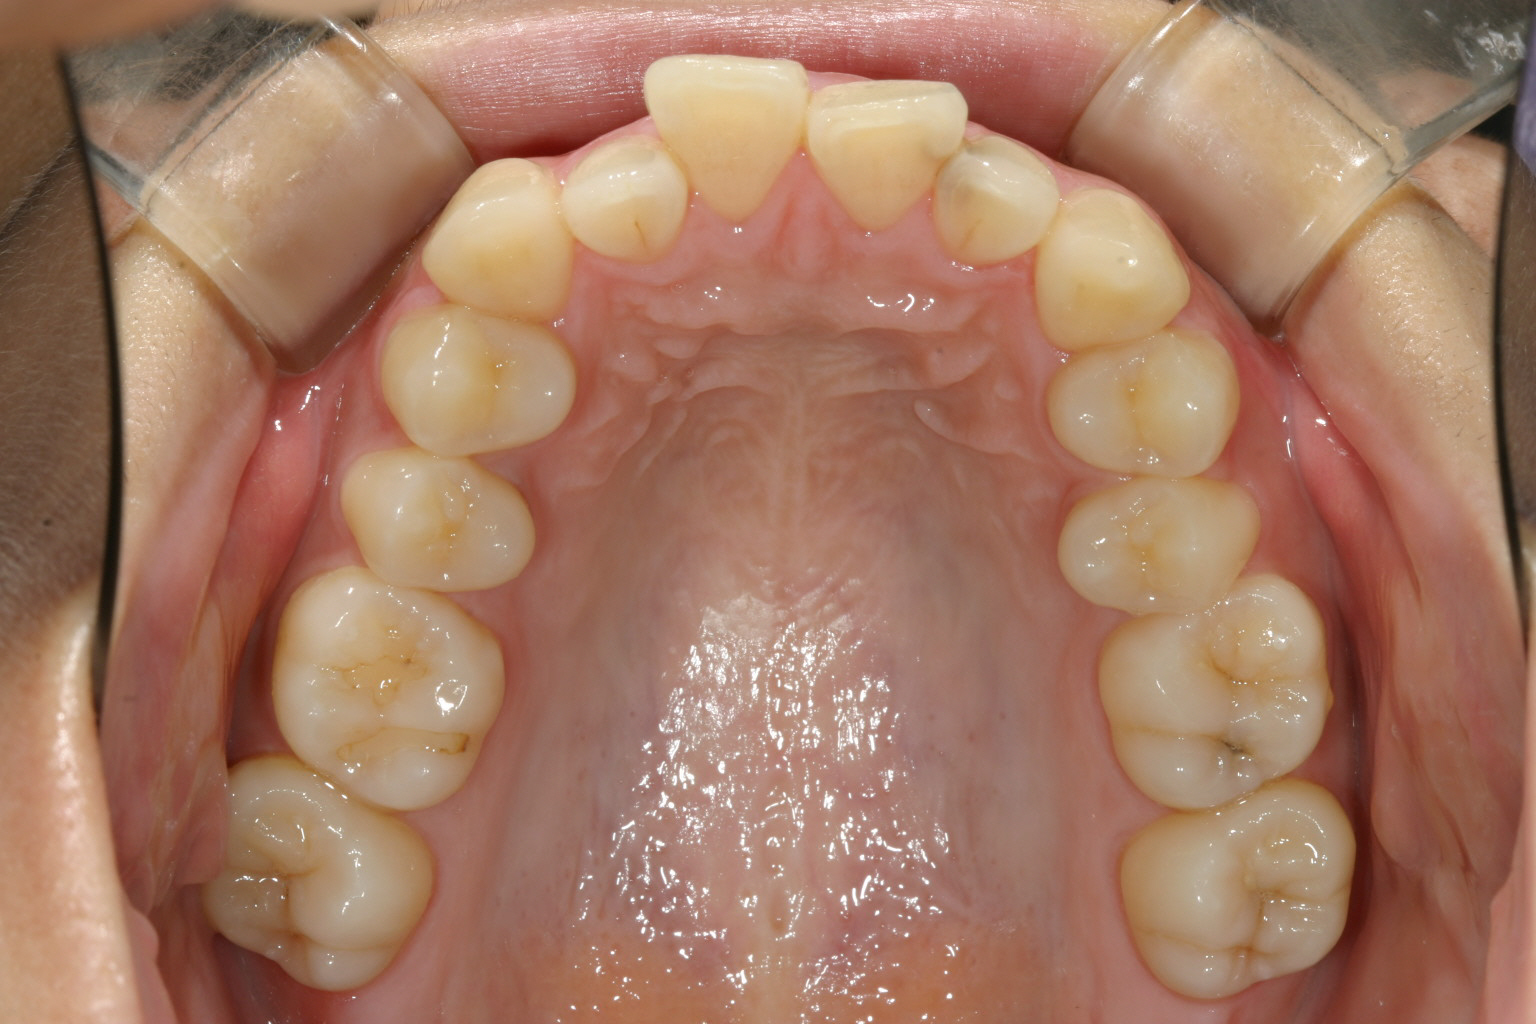

前歯に少しガタガタが見られます。

下顎にもガタガタが見受けられます。奥歯が全体的に内方へ倒れ歯列がV字形になってる為前歯がガタガタしているのです。